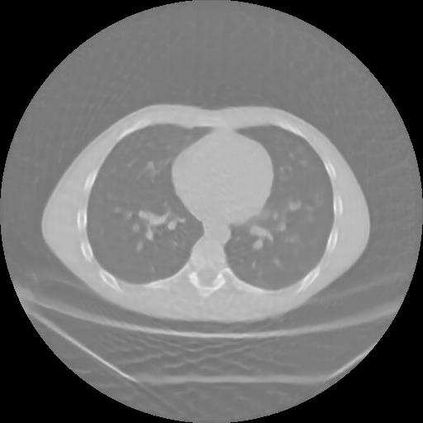

Sparse-view computed tomography (CT) is known as a widely used approach to reduce radiation dose while accelerating imaging through lowered projection views and correlated calculations. However, its severe imaging noise and streaking artifacts turn out to be a major issue in the low dose protocol. In this paper, we propose a dual-domain deep learning-based method that breaks through the limitations of currently prevailing algorithms that merely process single image slices. Since the scanned object usually contains a high degree of spatial continuity, the obtained consecutive imaging slices embody rich information that is largely unexplored. Therefore, we establish a cascade model named LS-AAE which aims to tackle the above problem. In addition, in order to adapt to the social trend of lightweight medical care, our model adopts the inverted residual with linear bottleneck in the module design to make it mobile and lightweight (reduce model parameters to one-eighth of its original) without sacrificing its performance. In our experiments, sparse sampling is conducted at intervals of 4{\deg}, 8{\deg} and 16{\deg}, which appears to be a challenging sparsity that few scholars have attempted before. Nevertheless, our method still exhibits its robustness and achieves the state-of-the-art performance by reaching the PSNR of 40.305 and the SSIM of 0.948, while ensuring high model mobility. Particularly, it still exceeds other current methods when the sampling rate is one-fourth of them, thereby demonstrating its remarkable superiority.